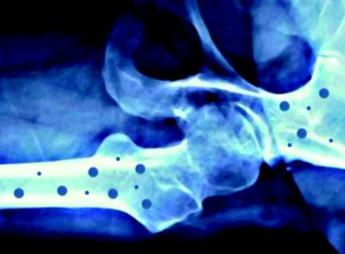

(Adnkronos) – In occasione della Giornata mondiale dell’osteoporosi, che si celebra il 20 ottobre sul tema ‘Dite no alle ossa fragili’, Feidos, Federazione italiana osteoporosi e malattie dello scheletro, rinnova il suo impegno per la salute delle ossa con nuove iniziative a supporto dei pazienti. L’osteoporosi – ricorda una nota – è una patologia che colpisce almeno 5 milioni di persone in Italia e 200 milioni nel mondo, e la cui incidenza è destinata a crescere nel prossimo futuro. Su questa malattia ormai globale, Feidos accende i riflettori sensibilizzando la popolazione sull’importanza di adottare sani stili di vita per migliorare lo stato di salute delle ossa, in particolare attraverso una corretta alimentazione, un’adeguata e regolare attività fisica, nonché prestando attenzione ai fattori di rischio individuali.

L’iniziativa ha il supporto incondizionato di Ibsa Farmaceutici Italia come main sponsor, e di Gedeon Richter, Organon, Accord Healthcare Italia, Ucb e Theramex come silver sponsor. Sono le aziende farmaceutiche che hanno scelto di sostenerne questi importanti progetti di informazione che, grazie a loro, possono essere portati avanti. L’osteoporosi – conclude la nota – è una malattia sistemica dell’apparato scheletrico, caratterizzata da una bassa densità minerale e dal deterioramento della micro-architettura del tessuto osseo, con conseguente aumento della fragilità ossea e del rischio di fratturarsi.